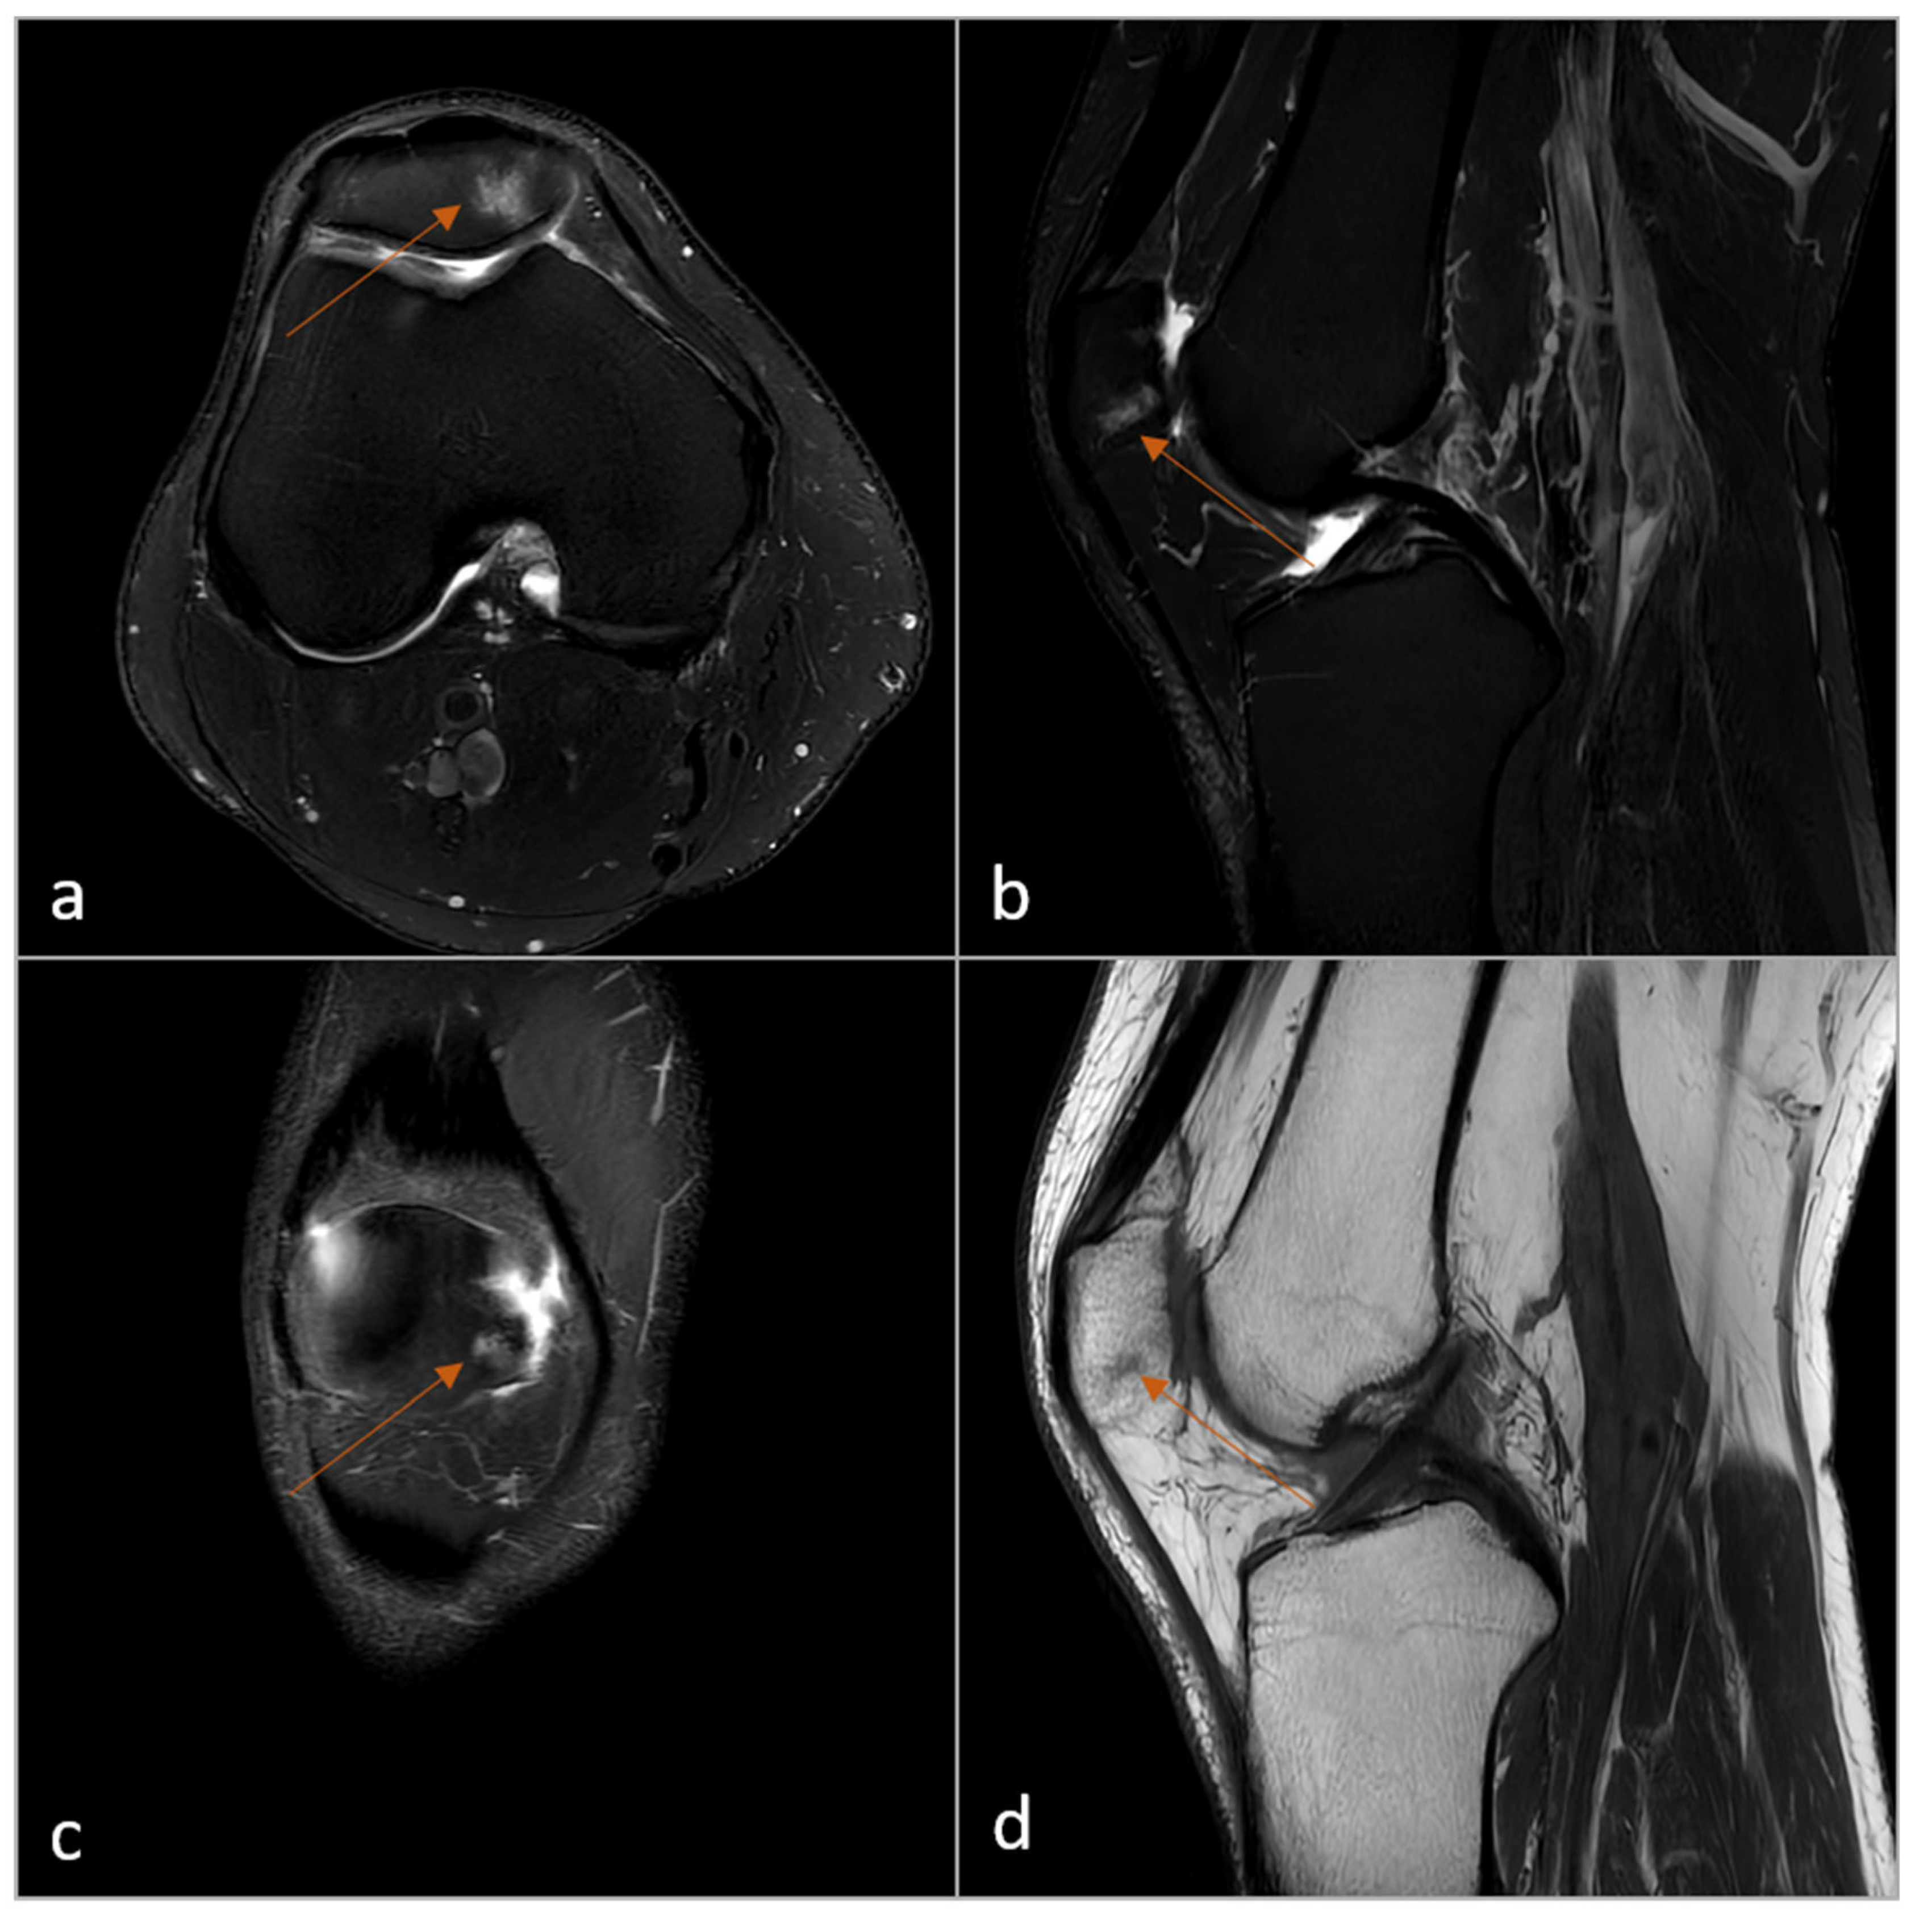

2.4. Subjective Image Analysis

3.3. Subjective Image Analysis